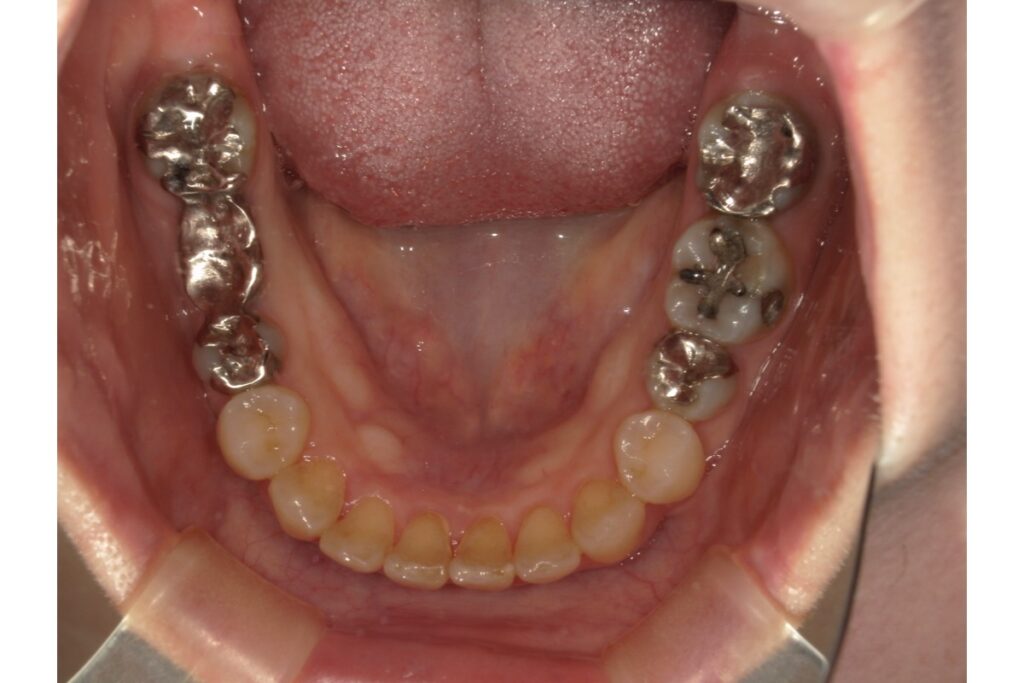

実際に補綴物の入っている治療の症例をご紹介します、インビザラインにて治療されました。

治療期間は約1年です。